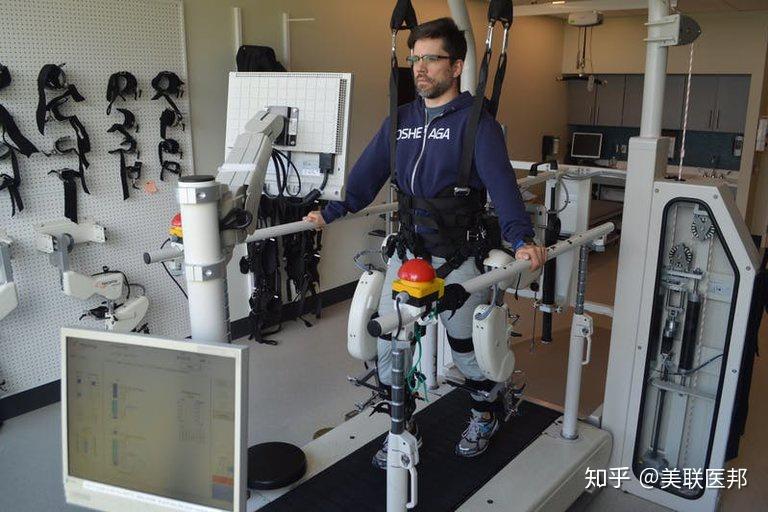

- 机器人步态训练:这种新兴技术用于脊髓损伤后的再训练行走能力。

机器人步态训练报道

https://www.zhihu.com/video/1042817426668462080

机器人步态训练报道

https://www.zhihu.com/video/1042817426668462080